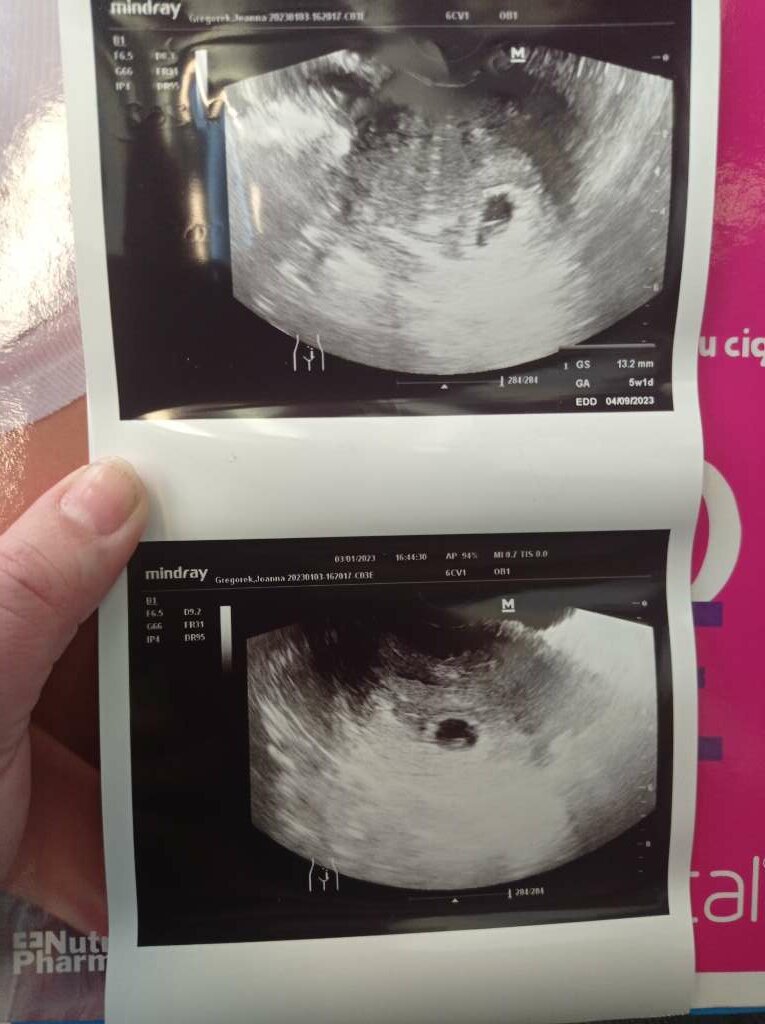

nie robilam juz bety u mnie w ogole jakos dziwnie. Bo poszlam do lekarza pierwszego rosno 5 tygodni po @. Powiedzial ze nuby to 2/3 tydzien ciazy bylo widac pecherzych. Kazal przyjsc za dwa tygodnie i wtedy powiedzial ze to 4/5 tydzien jest cialko zolte nie ma zarodka. Wystraszylam sie na drugi dzien poszlam do kolejnego i powiedzial ze to 5 tydzien i 1 dzien i jest zarodek. I tak kolejno wyszly zdjecia usg od 2 lekarzy.A beta na jakim poziomie? Z ciekawości spytam. Bo do wizyty u lekarza prawie tydzień a nie mogę się doliczyć Bo z bety wychodzi mi że 6 tydz. Z miesiączki że 4/5 mc

Może ma znaczenie dobra aparatura i umiejętnośc szukanianie robilam juz bety u mnie w ogole jakos dziwnie. Bo poszlam do lekarza pierwszego rosno 5 tygodni po @. Powiedzial ze nuby to 2/3 tydzien ciazy bylo widac pecherzych. Kazal przyjsc za dwa tygodnie i wtedy powiedzial ze to 4/5 tydzien jest cialko zolte nie ma zarodka. Wystraszylam sie na drugi dzien poszlam do kolejnego i powiedzial ze to 5 tydzien i 1 dzien i jest zarodek. I tak kolejno wyszly zdjecia usg od 2 lekarzy.